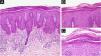

(A) Regular acanthosis, hypogranulosis, parakeratosis, dilated capillaries in the papillary dermis (Hematoxylin & eosin, ×100). (B) Parakeratosis and Munro’s microabscesses (B, Hematoxylin & eosin, ×200). (C) Higher magnification showing parakeratosis and Munro’s microabscesses (C, Hematoxylin & eosin, ×400).

A 62-year-old male presented with plaques with moderate infiltration and mild scaling on the back, frontal, and pre-auricular regions for two months (Fig. 1). He had a previous diagnosis of stage IV gastric adenocarcinoma with liver metastasis and has been treated with nivolumab 240 mg every two weeks for six months with partial response. He had no history of previous cutaneous diseases and denied a family history of immune-mediated disorders. The hypothesis of nivolumab-induced psoriasis was raised. Skin biopsy revealed regular acanthosis, hypogranulosis, parakeratosis, dilated capillaries in the papillary dermis, and Munro’s microabscesses compatible with psoriasis (Fig. 2). Skin lesions were refractory to topical steroids and due to intense pruritus, the patient stopped cancer treatment. Because of the lack of response to topical steroids, difficulty in adhering to phototherapy, and contraindication for the use of acitretin and methotrexate due to liver metastasis, the patient started Guselkumab 100 mg at weeks 0-, 4-, and every 8-weeks. After two applications, significant improvement was observed (Fig. 3). After 12-months skin lesions completely resolved, but malignant disease progressed with new liver lesions. Nivolumab was restarted, and skin remains clear with no significant adverse events due to Guselkumab.